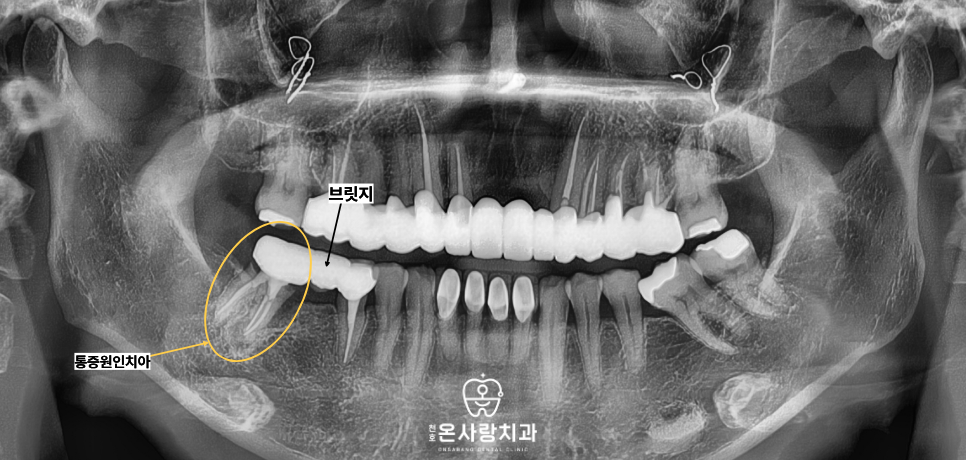

안쪽의 치아에 손상이 가지 않도록

조심스럽게 보철물을 벗겨낸 뒤

안쪽에 숨어 있던 기둥 치아들의

상태를 면밀히 살폈습니다.

확인 결과 통증의 주원인이었던

큰 어금니 치아는 이미 손상이 심각하여,

더 이상 치아로서의 기능을

수행하기 어려운 상태였습니다.

반면 연결되어있던 작은어금니는

다행히도 내부 상태가 양호하였습니다.

작은 어금니 치아의 경우

브릿지를 잘라낸 뒤,

기존 크라운을 깨끗하게 다듬는

폴리싱 과정을 거치면

충분히 다시 사용할 수 있을 정도로

건강하다는 판단을 내렸습니다.